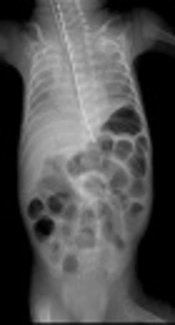

Clinical Presentation in a Series of Eight Children with Abdominal Tuberculosis: Experience of a Single-Center in Turkey

Merve Usta*,

Nafiye Urganci,

Nazan Dalgic,

Nuray Uslu Kızılkan,

Tugce Kurtaraner,

Cetin Ali Karadag